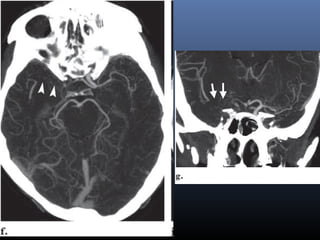

HYPER DENSE MCA SIGN

 ↑ed density of an MCA

segment due to Ac

thrombus.

 Can be seen within 90 mins

 Specificity 100% ,

Sensitivity only 30% .

 False positive : High

hematocrit or calcified

atherosclerotic disease

 But in such cases the

hyperattenuation is usually

bilateral.

MCA dot sign

 Hyper density of sylvian MCA branches indicative of

M2 or M3 thrombus (sensitivity in 52% & specificity of

92% )

Hyper dense basilar artery.

 Indicates acute basilar artery thrombosis.

OBSCURATION OF LENTIFORM NUCLEUS

Obscuration of the

lentiform nucleus, also

called blurred basal

ganglia, is an important

sign of infarction.

It is seen in middle

cerebral artery infarction

and is one of the earliest

and most frequently

seen signs.

The basal ganglia are

almost always involved

in MCA-infarction.